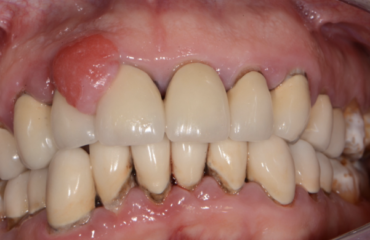

La parodontite o piorrea è una delle malattie più diffuse al mondo ed è caratterizzata da un’infiammazione cronica causata da microrganismi specifici che si trovano nella placca batterica che provoca, se non curata, la distruzione dei tessuti di sostegno dei denti (cioè del parodonto) e conseguentemente la loro perdita.La parodontite è una malattia che può […]